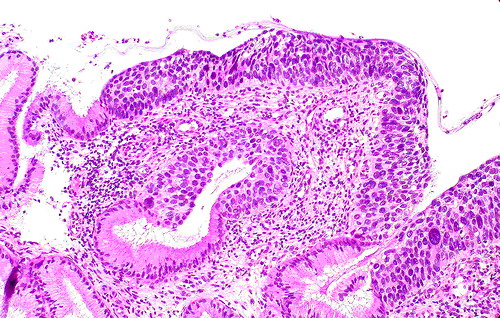

举例来说,慢性宫颈炎(宫颈糜烂)与宫颈癌在妇科阴道镜检查时观察到的表现可以相似。行宫颈刮片的细胞检查时看到的也可以相似(图1、2)。最后采取组织行病理切片检查,也是有相似之处,不是容易做出100%鉴别的(图3、4)。这样看来,如果仅一次检查(或一家医院检查),就肯定是癌,而行手术切除,是不慎重的,错误率是高的。最好是如果要手术切除,应到第二家医院或第二个医生核实后进行下一步治疗。

图4 宫颈癌时看到的切片